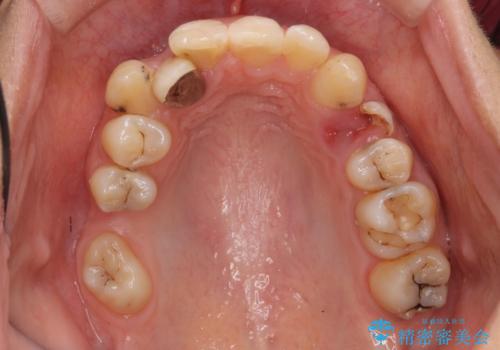

あきらめないで!!虫歯でボロボロでも大丈夫! 非抜歯矯正と虫歯、インプラント治療で見違える歯並びに。

虫歯が多数、また奥歯も欠損してしまっていました。

左下の親知らず、左上の小臼歯が残根状態で一本抜いたほかは抜かずに矯正しました。

①保存不可能な歯は抜歯しそのすき間を矯正で閉じる

②右上の親知らずは活かしてブリッジの支台にする

という、予算がかからないように歯を保存する治療計画を立てました。